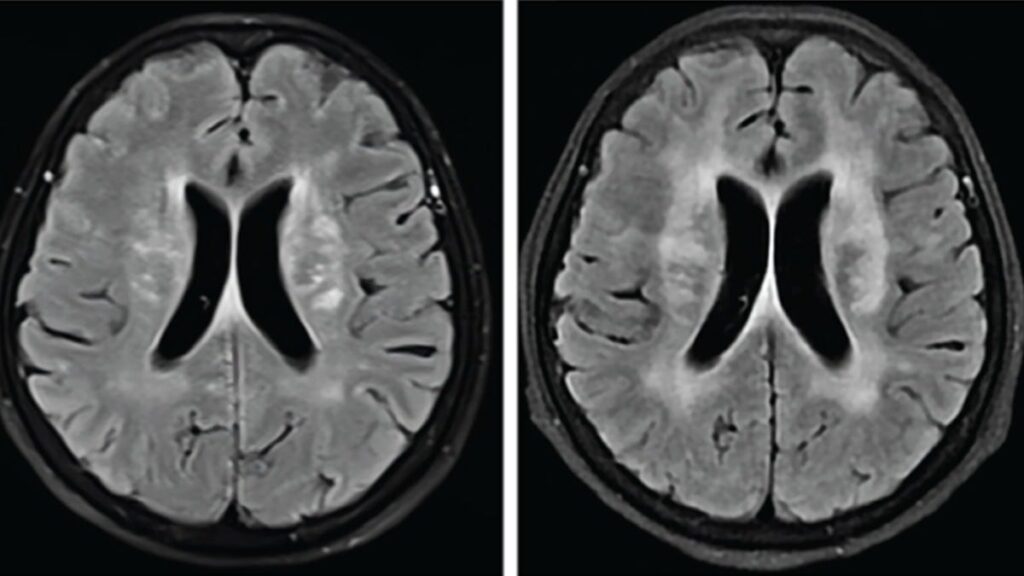

Doktorlar ilk olarak menenjitten şüphelendi. Yapılan MR taramasında beyninde çok sayıda lezyon görüldü ve bu da enfeksiyon olasılığını artırdı. Ancak iki hafta süren antibiyotik tedavisine rağmen hastanın durumu kötüleşmeye devam etti.

Hastaya hemen antiparaziter ilaç olan albendazol verildi. İki hafta içinde konuşma yetisini geri kazanan hastanın sağlığı hızla düzelmeye başladı. Dört ay sonraki kontrollerde, beyindeki lezyonların büyük ölçüde küçüldüğü ve hastanın neredeyse tamamen iyileştiği gözlemlendi.